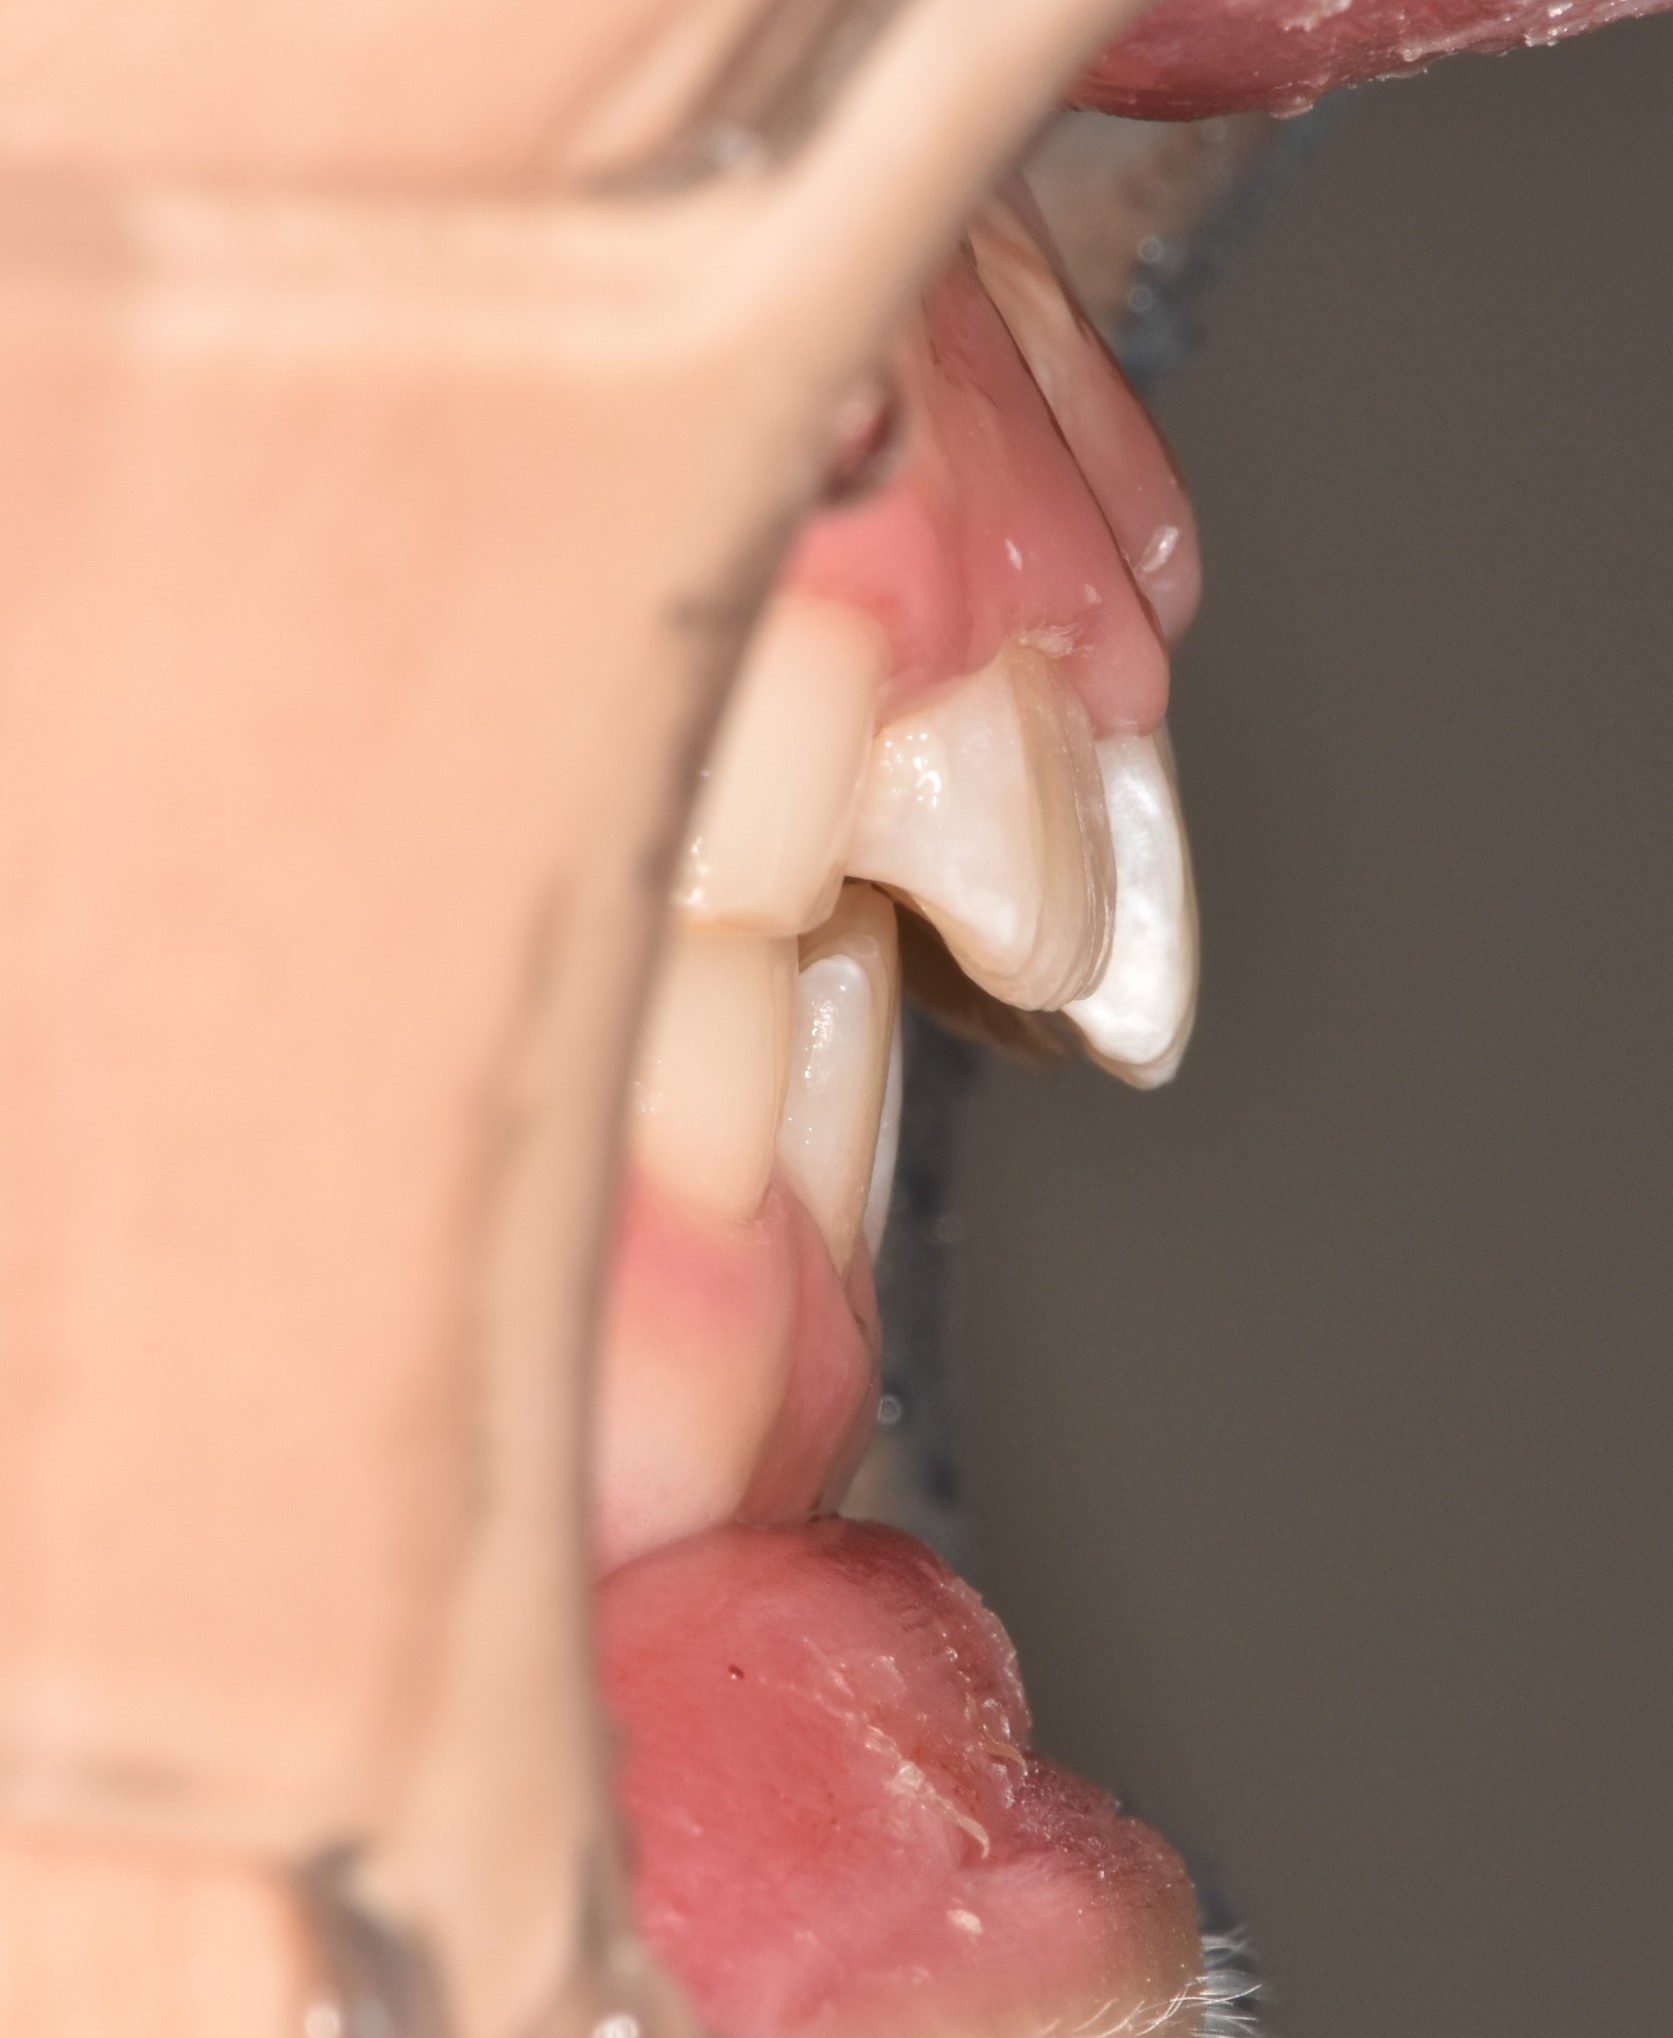

투명교정장치 착용중. 장치를 착용하여도 티가 나지 않습니다. 아이는 정말 성실하게 장치를 잘 껴주었습니다.

1년 후, 교정완료하였습니다. 튀어나온 앞니는 가지런히 넣었고 악궁을 확장하여 충분한 송곳니, 어금니의 맹출공간을 확보하였습니다.